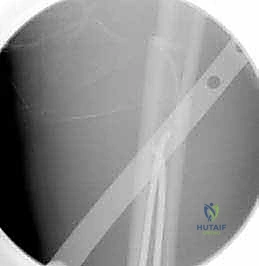

الخطوة الثالثة: تشكيل وإدخال المسامير (TENs)

هنا تبرز مهارة الجراح. يتم ثني مسامير التيتانيوم بزاوية وانحناء محددين مسبقاً. يتم إدخال المسمار الأول ببطء داخل التجويف النخاعي، ودفعه للأعلى حتى يعبر منطقة الكسر ويستقر في الجزء العلوي من عظم الفخذ. ثم يتم إدخال المسمار الثاني من الجهة المقابلة ليتقاطع مع الأول ويشكلان حرف (X) أو شبكة داعمة داخل العظم. هذا التقاطع يولد قوة ميكانيكية تثبت الكسر بقوة من الداخل.